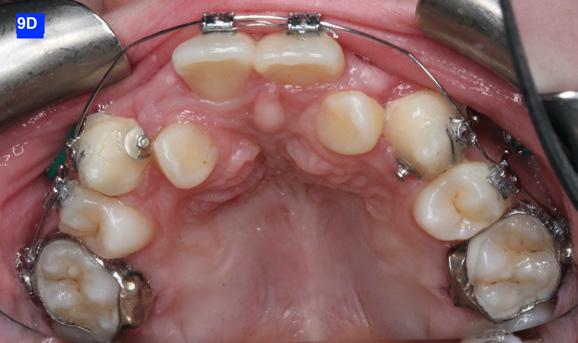

The maxillary cuspids were erupting mesially to the lateral incisors, with very little space to accommodate both teeth without an odontectomy. The expansion was continued (1/4 turn 2x per week), and an attempt was made to create more space for erupting cuspids with an open coil spring (OCS) – between the central incisors and the cuspids (Molar distalization spring, a .010 x .045 - Ortho Organizers). The OCS was measured and cut 4.0 mm longer than the available space. The maxillary arch wire was a .018 SS. An elastomeric chain (EC) was attached from the Hyrax to the lingual button on the lateral incisors. It was necessary to first pull the lateral incisors away from the alveolar process to prevent the break down of the buccal cortical bone around the cuspids (Figure

B, C).

4-A, Figure 3A: The patient transferred to our office, frontal view Figure 3B: The patient transferred to our office, maxilla, occlusal view Figure 3C: The patient transferred to our office, mandible, occlusal view Figure 4A: OCS, frontal view Figure 4B: Hyrax, occlusal view Figure 4C: Retraction of maxillary lateral incisors

The eruption of maxillary cuspids was expedited with the Adrian “U” bend spring5 where the cardinal arch wire was a .016 SS and the secondary arch wire a .014 NiTi5. Since we were working with the PSL brackets, a combination of larger diameter wires would not allow the latch to close (Figure 5–A, B, C). Also note the progress in retraction of the lateral incisors (Figure 5-D).

Figure 5A: Adrian “U” bend spring, frontal view Figure 5B: Adrian “U” bend spring, right lateral view Figure 5C: Adrian “U” bend spring, left lateral view Figure 5D: Continuation of retraction, occlusal view Figure 6A: OCS between the central incisors an the cuspids Figure 6B: Retraction of the lateral incisors is completed Figure 7A: Starting treatment on the mandibular arch, frontal view